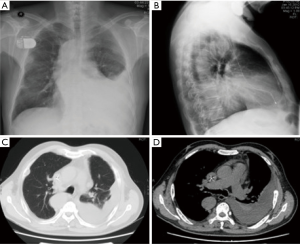

Chest radiograph (Figure 1) showed left pleural effusion and the computed tomographic image of the chest (Figure 1) showed left massive pleural effusion, pulmonary atelectasis of left lower lobe, and multiple destruction of bones in bilateral costal bones, thoracic vertebra and left scapula. To detect the origin of malignancy, PET-CT showed multiple abnormally high glucose metabolic sites in bones, ossification, osteolysis and pathologic fracture, left pleural effusion and pulmonary atelectasis of left lower lobe.